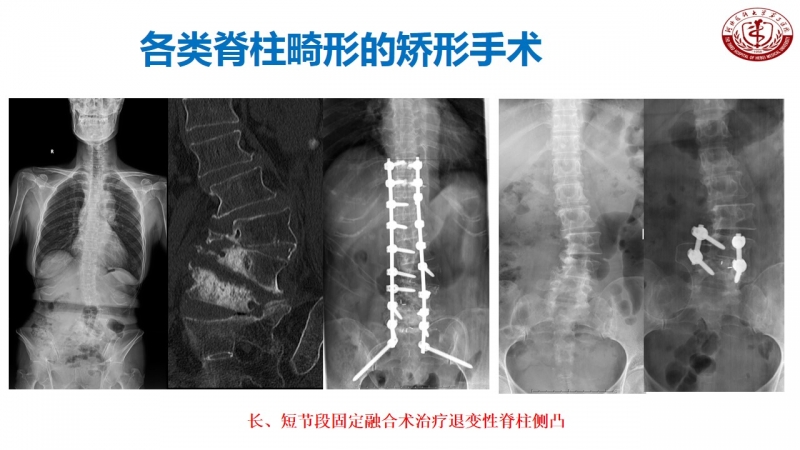

作为脊柱外科的主任,丁文元教授时刻不忘科室的建设和发展。目前,河北医科大学第三医院脊柱外科共有33人,其中主任医师9人,副主任医师4人,主治医师11人,分三个病区,共120张床位,年门诊量66000余人次,年手术量4500余台,并开展了一系列脊柱高难手术,如复杂脊柱畸形截骨矫形术、复杂严重颈椎病前后路手术、胸腰椎前后路手术、上颈椎腰骶部复杂手术以及脊柱各种微创手术。

脊柱外科目前所开展的诊疗技术(滑动查看)